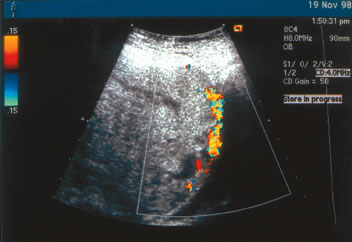

Rosemond and Kepple84 described a case in which abnormal sonographic findings were appreciated only with transvaginal color Doppler sonography. When Doppler flow studies of the normal retroplacental clear space are performed, multiple venous flow signals are seen in this area.84,86 Absence of this space represents abnormal placentation. In a case of placenta percreta diagnosed at our institution (Fig. 2), the interface between the placenta and the maternal urinary bladder is essentially absent. Transabdominal color Doppler studies were diagnostic in this patient, and placenta percreta was subsequently confirmed at cesarean delivery.

Fig. 2. Placenta percreta diagnosed antenatally by transabdominal color Doppler ultrasound. Note the loss of interface between the placenta and the maternal urinary bladder.(J.S. Sholl, MD; ultrasonographer)